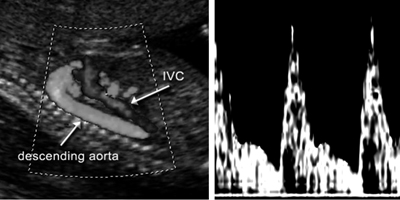

Κατιούσα αορτή του εμβρύου

Η Doppler εξέταση γίνεται στο τμήμα άνωθεν του διαφράγματος, με γωνία 45°.

Το χαρακτηριστικό της κατιούσας αορτής είναι ότι ο δείκτης παλμικότητας παραμένει

σταθερός κατά την κύηση (εικόνα 8). Οι ταχύτητες ροής της κατιούσας αορτής είναι

το άθροισμα της ροής αίματος και της αντίστασης στη ροή των νεφρών, των άλλων

κοιλιακών οργάνων της μηριαίων αρτηριών και του πλακούντα. Το 50% του αίματός

της διανέμεται στην κατιούσα και στην ομφαλική αρτηρία. Αν και όπως προαναφέρθηκε

το PI της ομφαλικής ελαττώνεται, αυτό της κατιούσας αορτής παραμένει σταθερό,

λόγω αγγειοσύσπασης που συμβαίνει ιδίως στα άκρα.

Εικόνα 8. Κατιούσα αορτή του εμβρύου.